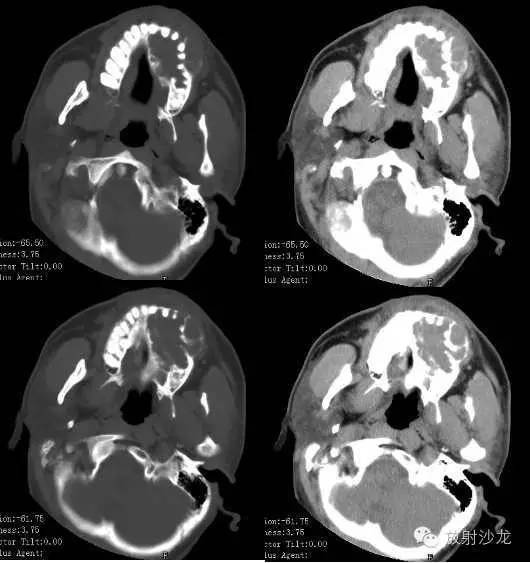

【术前CT扫描图像】

术前CT诊断:左侧下颌骨不规则膨胀性骨质破坏区,内可见软组织及残存骨嵴,病灶累及牙槽骨及筛窦壁,考虑造釉细胞瘤可能性大。